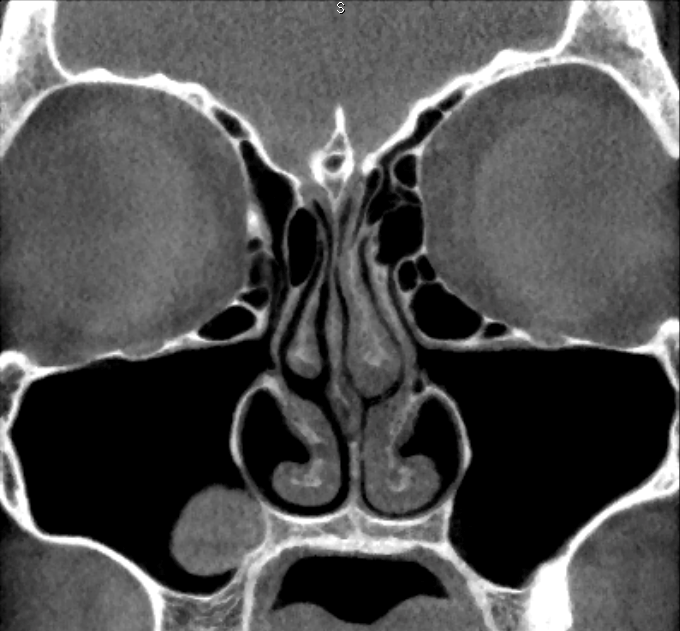

First, the coronal planes were assessed, as this is a common approach in most published studies [36] (Figure 1 [Fig. 1]). In a second step we inspected the axial and sagittal plane to differentiate Haller cells from simple bone crests. Bone crests often mimic complete cells when only viewed in one plane or in summarized two-dimensional radiographs (Figure 2 [Fig. 2], Figure 3 [Fig. 3]).

Figure 1: Bilateral Haller cells on coronal plane of CBCT